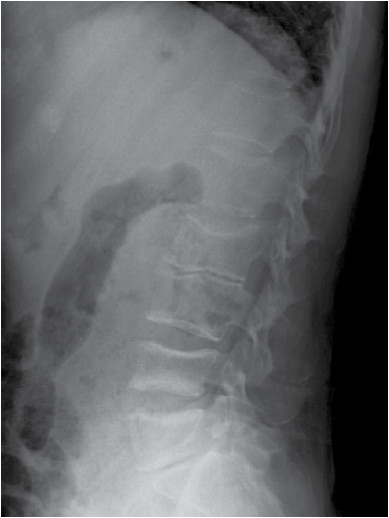

En los paraclínicos iniciales se evidencian fracturas vertebrales por insuficiencia en L2, L4 y L5, en radiografía simple de columna (figura 1), que se caracterizaron con resonancia magnética (figura 2). En el estudio de osteoporosis secundaria, se descarta hiperparatiroidismo, alteración del perfil tiroideo, hepático y renal. No se evidencia pico monoclonal en la electroforesis de proteínas. Se encuentra hipoalbuminemia y perfil fosfocálcico con déficit de vitamina D (tabla). Por lo que se considera osteoporosis secundaria a enfermedad inflamatoria intestinal. Se inicia manejo interdisciplinario con nutrición, terapia física, clínica del dolor y gastroenterología. Se inicia acompañamiento nutricional y rehabilitación física, suplencia de calcio y vitamina D y teriparatida, con mejoría de la sintomatología.

Figura 2. Las secuencias T1 y T2 configuración bicóncava de los cuerpos vertebrales con pérdida de altura e hipointensidad de la médula ósea por fracturas antiguas de cuerpos vertebrales de L4 y L5. Osteocondrosis desde L2-L4 hasta L5-S1 con deshidratación de discos intervertebrales y pérdida de su altura. Fractura antigua de cuerpo vertebral T11 con depresión de platillo vertebral superior, discreto acuñamiento anterior y nódulo Schmorl. La secuencia STIR sugiere que las fracturas son antiguas, aunque hay discreta hiperintensidad en L4 que podría corresponder a edema óseo.